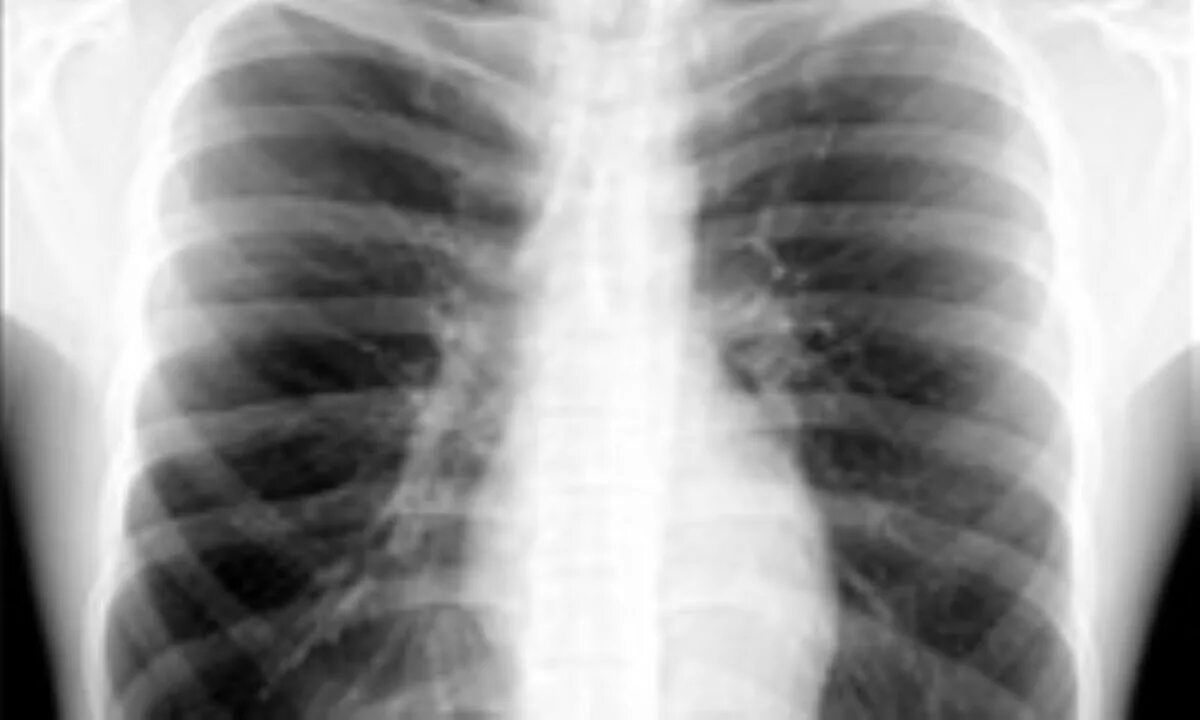

Метатуберкулезные изменения в легких что это означает